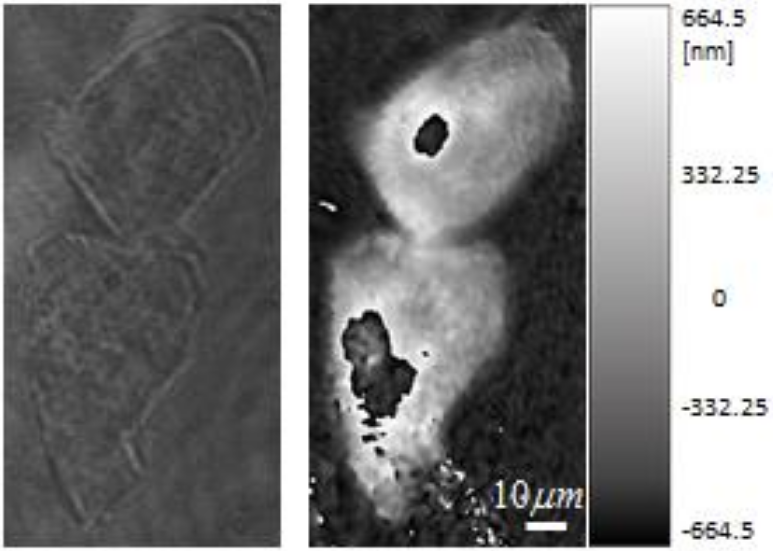

Laforest T., Künzi M., Kowalczuk L., Carpentras D., Behar-Cohen F. and Moser C. , Transscleral optical phase imaging of the human retina, Nature Photonics, March 2020. |

Laforest T., Künzi M., Kowalczuk L., Carpentras D., Behar-Cohen F., Moser C., Transscleral Optical Phase Imaging of the Human Retina – TOPI, pre print, May 15th, 2019. |

Laforest T., Carpentras D., Kunzi M., Kowalczuk L., Behar-Cohen F., Moser C., A new microscopy for imaging retinal cells, arXiv:1712.08472. |

Kowalczuk L., Dornier R., Kunzi M., Iskandar A., Misutkova Z., Gryczka A., Navarro A., Jeunet F., Mantel I., Behar-Cohen F., Laforest T., Moser C., in vivo Retinal Pigment Epithelium Imaging using Transscleral OPtical Imaging in healthy eyes, Ophthalmology Science, 100234 (2022). |

dos Santos F., Laforest T., Künzi M., Kowalczuk L., Behar-Cohen F., and Moser C., Fully automated detection, segmentation, and analysis of in vivo RPE single cells, Eye, June 2020. |

Govindahari V., Dornier R., Ferdowsi S., Moser C., Mantel I., Behar-Cohen F., Kowalczuk L., High-Resolution Adaptive Optics-Trans-scleral Flood Illumination (AO-TFI) Imaging of Retinal Pigment Epithelium (RPE) in Central Serous Chorioretinopathy (CSCR), Scientific Reports, 14.1 (2024):13689. doi: 10.1038/s41598-024-64524-4. |

Kowalczuk L., Dornier R., Navarro A., Jeunet F., Moser C., Behar-Cohen F., Mantel I., Adaptive Optics-Transscleral Flood Illumination Imaging of Retinal Pigment Epithelium in Dry Age-Related Macular Degeneration, Cells (2025), 14(9), 633. doi: 10.3390/cells14090633. |